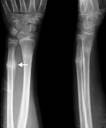

1 2 3

Рис..41. 1 – неправильно сросшийся перелом, избыточная костная мозоль; 2 – ложный сустав; 3 – оссифицирующий| миозит.